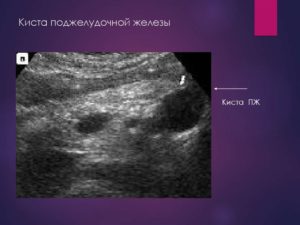

- УЗИ позволяет определить размеры кистозных полостей, их количество, наличие осложнений;

Высокоинформативны инструментальные методы визуализации кисты. УЗИ поджелудочной железы позволяет оценить размеры образования, а также косвенные признаки осложнений: в случае нагноения определяется неравномерность эхосигнала на фоне полости, при малигнизации – неоднородность контуров.

При ультразвуковом исследовании можно диагностировать кисту всех отделов поджелудочной — головки, тела и хвоста. Эндоскопическое УЗИ дополнительно позволяет определить доброкачественность или злокачественность образования.